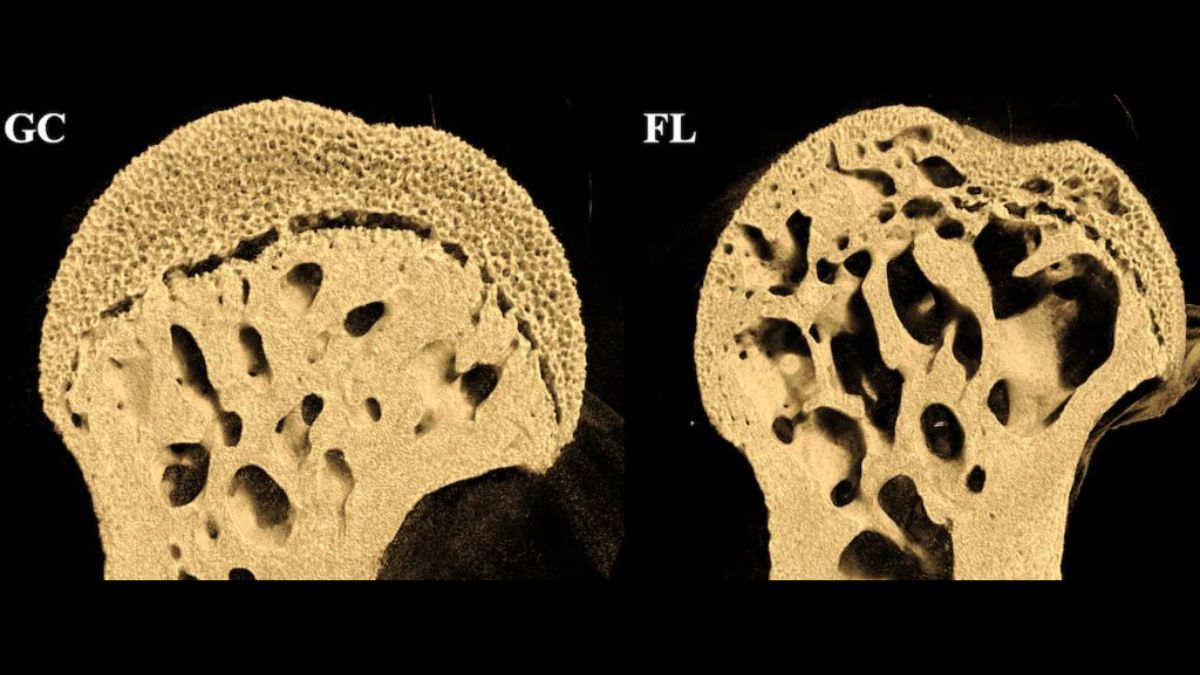

La NASA a envoyé des souris dans l’espace, elles sont revenues avec des trous dans les os

Les souris qui ont été envoyées dans l’espace ont subi une importante perte de densité osseuse, notamment dans les parties inférieures de leur corps. The post La NASA a envoyé des souris dans l’espace, elles sont revenues avec des trous dans les os appeared first on Daily Geek Show.

Les souris qui ont été envoyées dans l’espace ont subi une importante perte de densité osseuse, notamment dans les parties inférieures de leur corps.